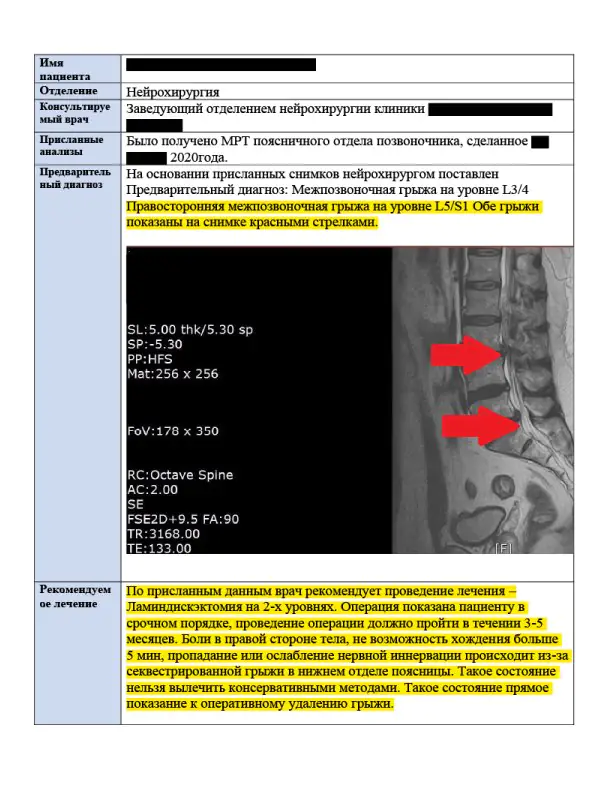

Для второго мнении врач прочитал снимки МРТ и подтвердил необходимость операции

Корейский нейрохирург предложил провести малоинвазивную операцию за место обычной, предложенной дома

В ответе врача описали операцию, написали срок госпитализации и примерную стоимость обследований и лечения